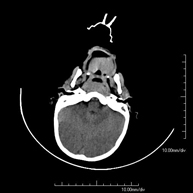

- TC Crani

Prova radiològica que consisteix en obtenir imatges del crani d'alta definició anatòmica (tronc cerebral, cerebel, cervell, calota cranial, etc. ) mitjançant l'ús d'un equip de TC (Tomografia Computeritzada). Indicacions: traumatismes, cefalea, trastorns de la memòria, pèrdua de força sobtada en una extremitat o meitat del cos. - TC Coll